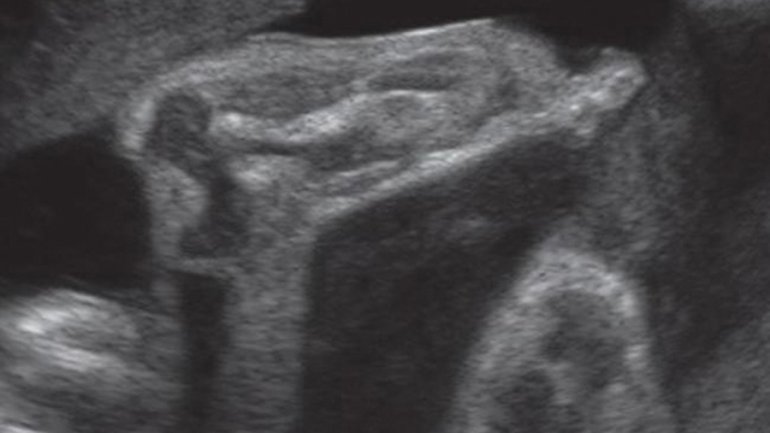

Ultraschall 8. SSW

Der Embryo misst jetzt etwa 15 Millimeter. Zur Orientierung: Der Embryo ist von vorne zu sehen, der Kopf liegt links im Bild. Arm- und Beinansätze lassen den Embryo wie einen kleinen Teddybären aussehen. Auf dem bewegten Ultraschall sind in dieser Woche die ersten, noch unkontrollieren Bewegungen zu erkennen.